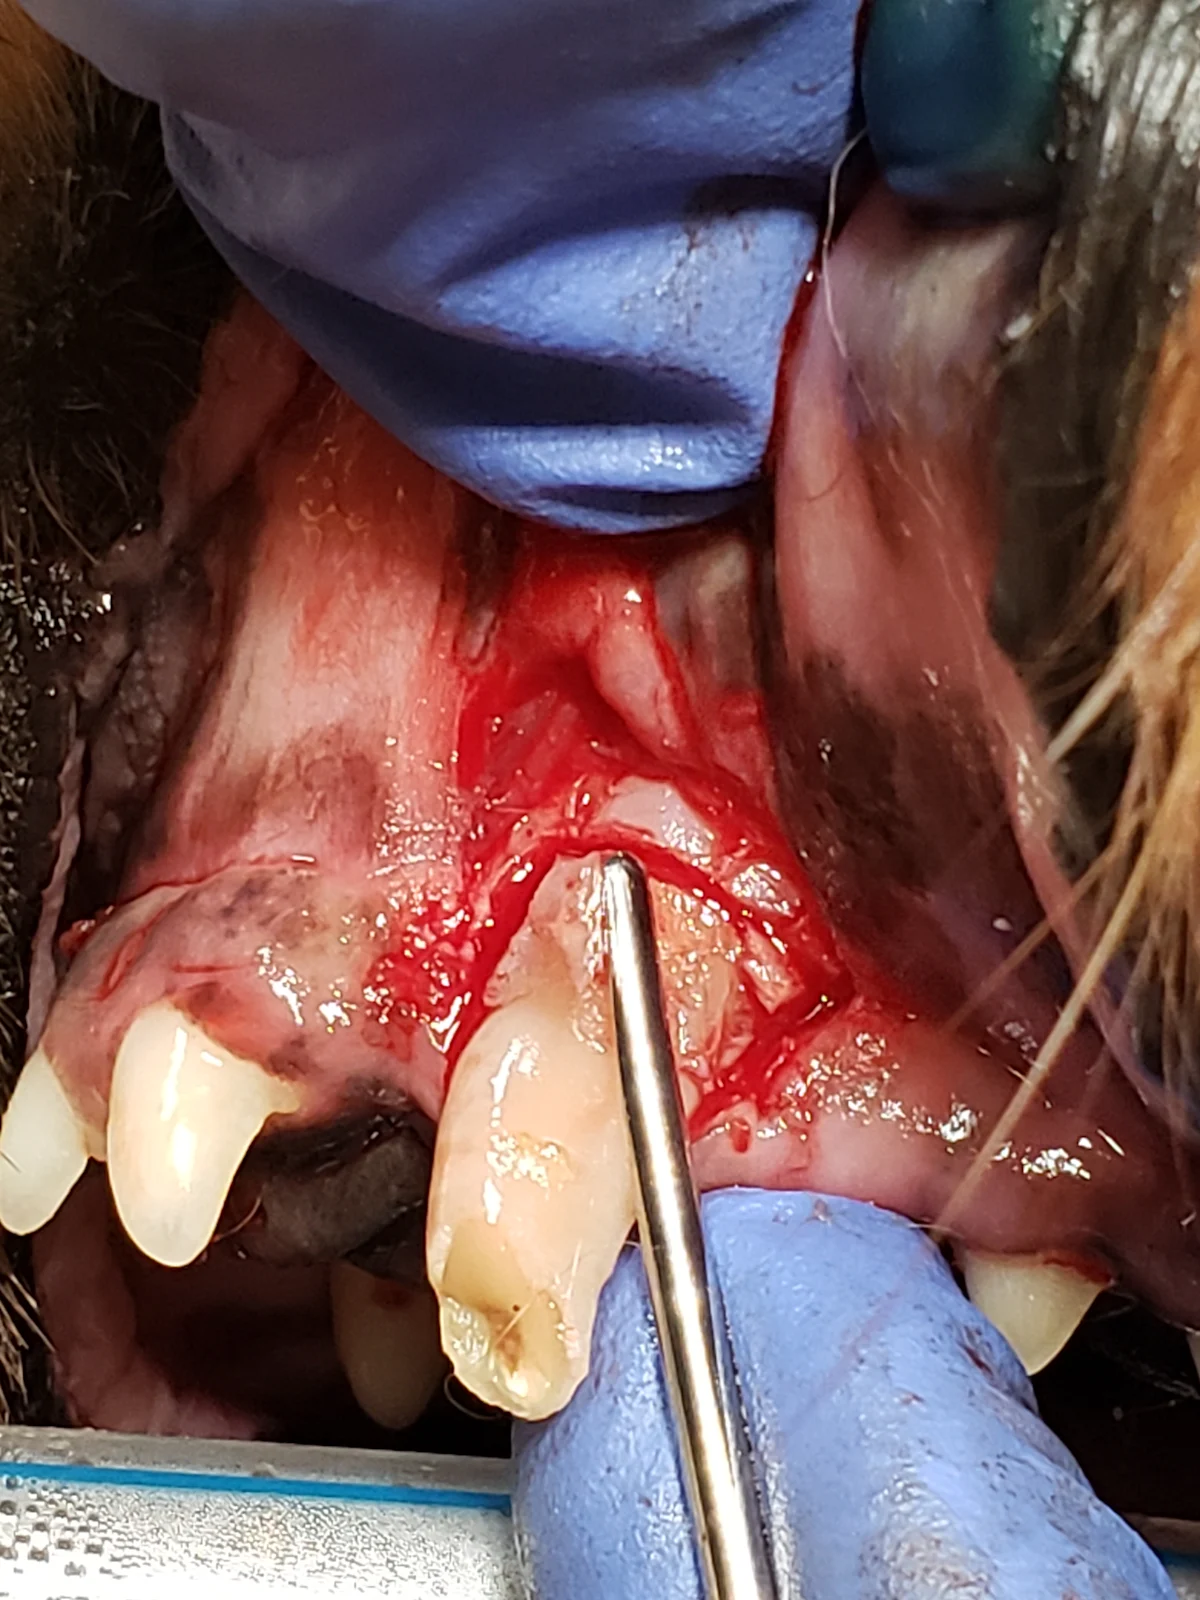

Step 2: Make Gingival Flap Releasing Incisions

Make releasing incisions for a full-thickness mucoperiosteal flap through the attached gingiva, past the mucogingival line, and at least a couple of millimeters into the alveolar mucosa to provide adequate exposure.

Rectangular Flap

A rectangular flap is created by making a mesial incision and a distal incision angled away from the tooth, following the distally curving position of the root. Releasing incisions should extend at least to the level of the widest part of the root and should be slightly divergent from each other, keeping the alveolar mucosa at the base of the flap wider than the coronal aspect with the attached gingiva, to provide enough tissue for closure. A flap wider at the gingival margin is important if an oronasal fistula is present. Making releasing incisions 1 to 2 mm from the outline of the tooth edge (dotted lines) places the incisions over bone, enhancing access to the periodontal ligament space and supporting the suture line following closure. In the author’s experience, this flap design provides optimal accessibility for tooth elevation and does not result in disruption of blood supply during healing.